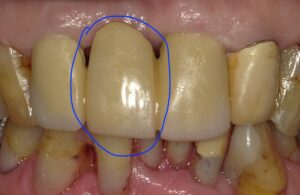

左の画像は真ん中の歯がありませんが右がブリッジをかぶせた画像で青丸部分に

歯ができています。

このようにブリッジは橋のようなものであり。橋義歯とも呼ばれます。